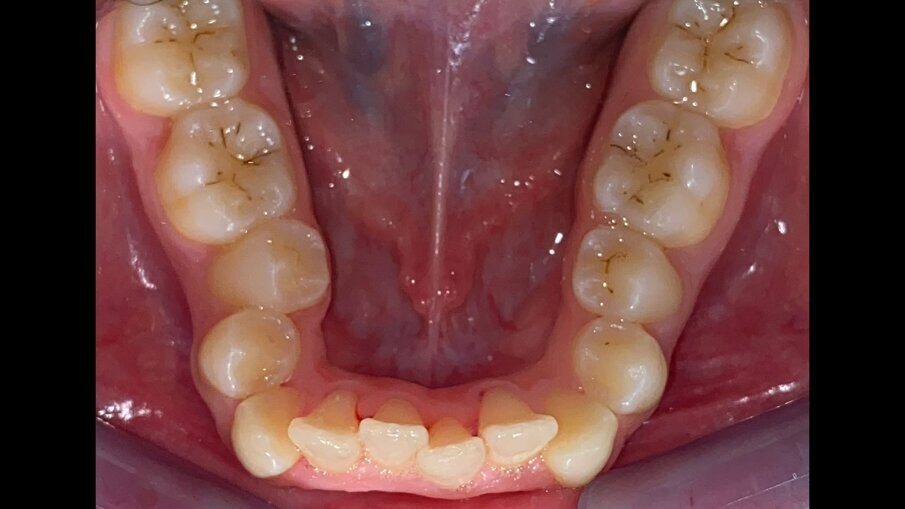

All’esame obiettivo intraorale si riscontra sul piano frontale un severo morso profondo con precontatto traumatico degli incisivi superiori contro la papilla retroincisiva e le rughe palatine anteriori durante la massima intercuspidazione, con overbite di 10 mm (Fig. 5). Dalle foto laterali si evidenzia una malocclusione di Classe II divisione 2 con scissor bite dell’elemento 1.5 (Figg. 6, 7), mentre dalle foto occlusali si rileva un grave affollamento con contrazione di entrambe le arcate maggiore nella zona premolare (Figg. 8, 9). L’analisi di Bolton mostra un eccesso superiore 3-3 di 2,34 mm (73,6%) e 6-6 di 2,76 mm (88,8%). L’analisi cefalometrica evidenzia una Classe II scheletrica, modello facciale normodivergente, angolo interincisale aumentato, incisivi superiori e inferiori retroinclinati (Fig. 10). La radiografia panoramica mostra la presenza dei germi dei terzi molari, assenza di parallelismo tra le radici dei premolari inferiori (Fig. 11) e una sovraeruzione degli incisivi inferiori che crea un doppio piano tra gli incisivi e i molari, segno di una curva di Spee molto profonda.

Fig. 9_Occlusale inferiore pre-trattamento.